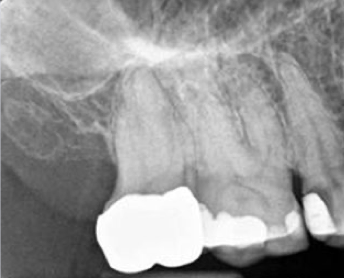

what radiographic analysis should be carried out during endodontic diagnosis?

A

• new periapicals (at least 2)

• bitewing

• cone beam-computed tomography